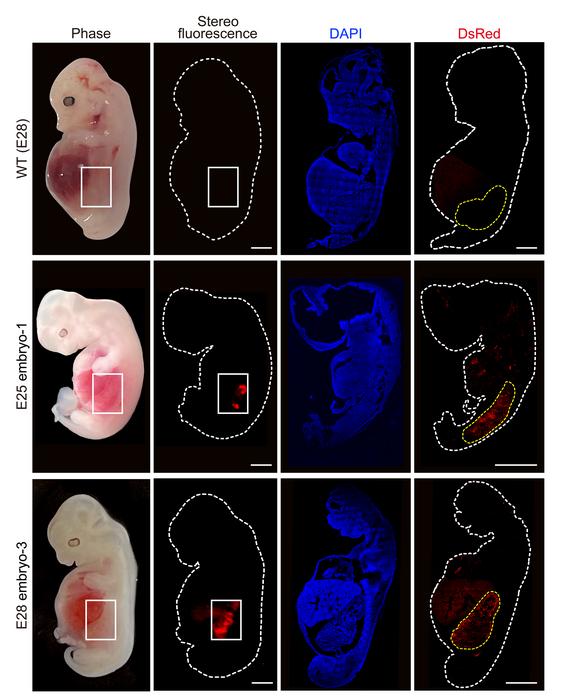

Altogether, the researchers transferred 1,820 embryos to 13 surrogate mothers. After either 25 or 28 days, they terminated gestation and extracted the embryos to assess whether the chimeras had successfully produced humanised kidneys.

The researchers collected five chimeric embryos for analysis (two at 25 days and three at 28 days post-implantation) and found that they had structurally normal kidneys for their stage of development and were composed of 50-60 per cent human cells.

At 25-28 days, the kidneys were in the mesonephros stage (the second stage of kidney development); they had formed tubules and buds of cells that would eventually become ureters connecting the kidney to the bladder.